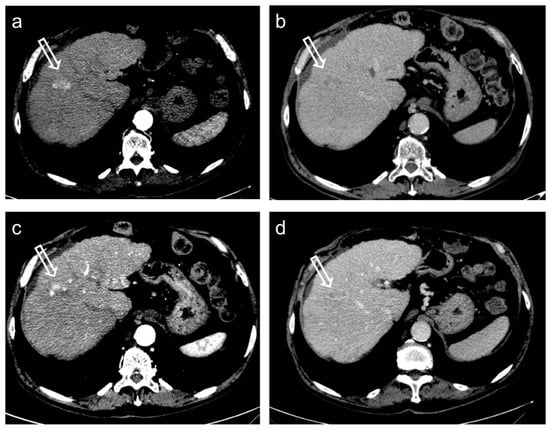

2. TACE Technique

3. Treatment Response Criteria